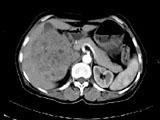

女,57岁,右腰部胀痛6月余,触及右侧腹部包块2月,CT平扫及增强如图所示,下列说法正确的是?(?)

• A.平扫时可见右侧腹部巨大的软组织肿块影,其内可见小片状的低密度影

• B.增强扫描肿块强化明显,其内可见无强化的低密度坏死灶

• C.考虑肿块来源于肝脏,是原发性肝癌,并挤压推移右肾

• D.考虑肿块来源于右肾,是巨大的肾癌,并挤压推移右肝,与其分界欠清

• E.考虑肿块来源于右肾,是肾血管平滑肌脂肪瘤,并挤压推移右肝,与其分界欠清